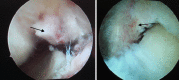

Methods: Both the avulsed bone block and the tibia bone bed were refreshed. The procedure was completed with the assistance of PCL director drill guide. The reduction and fixation using high-strength line were used to fix the avulsed bone by from posterior middle portal. Rehabilitation began early postoperatively.